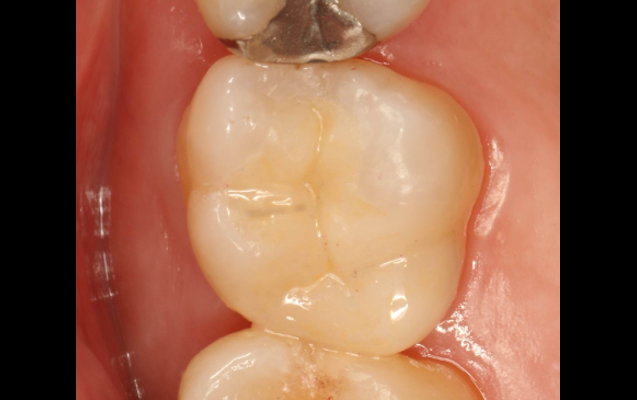

(実際の症例)

ダイレクトボンディングによる治療は、セラミックによる被せ物(クラウン)や詰め物(インレー)に比べて、歯を削る量を抑えることができる手法です。

当院では、色や透明感の異なる約十種類のプラスチックの中から、患者様の歯に合わせ選んだ多種類のプラスチックを重ね合わせていきます。従来の治療では困難であった自然な歯を再現可能としています。